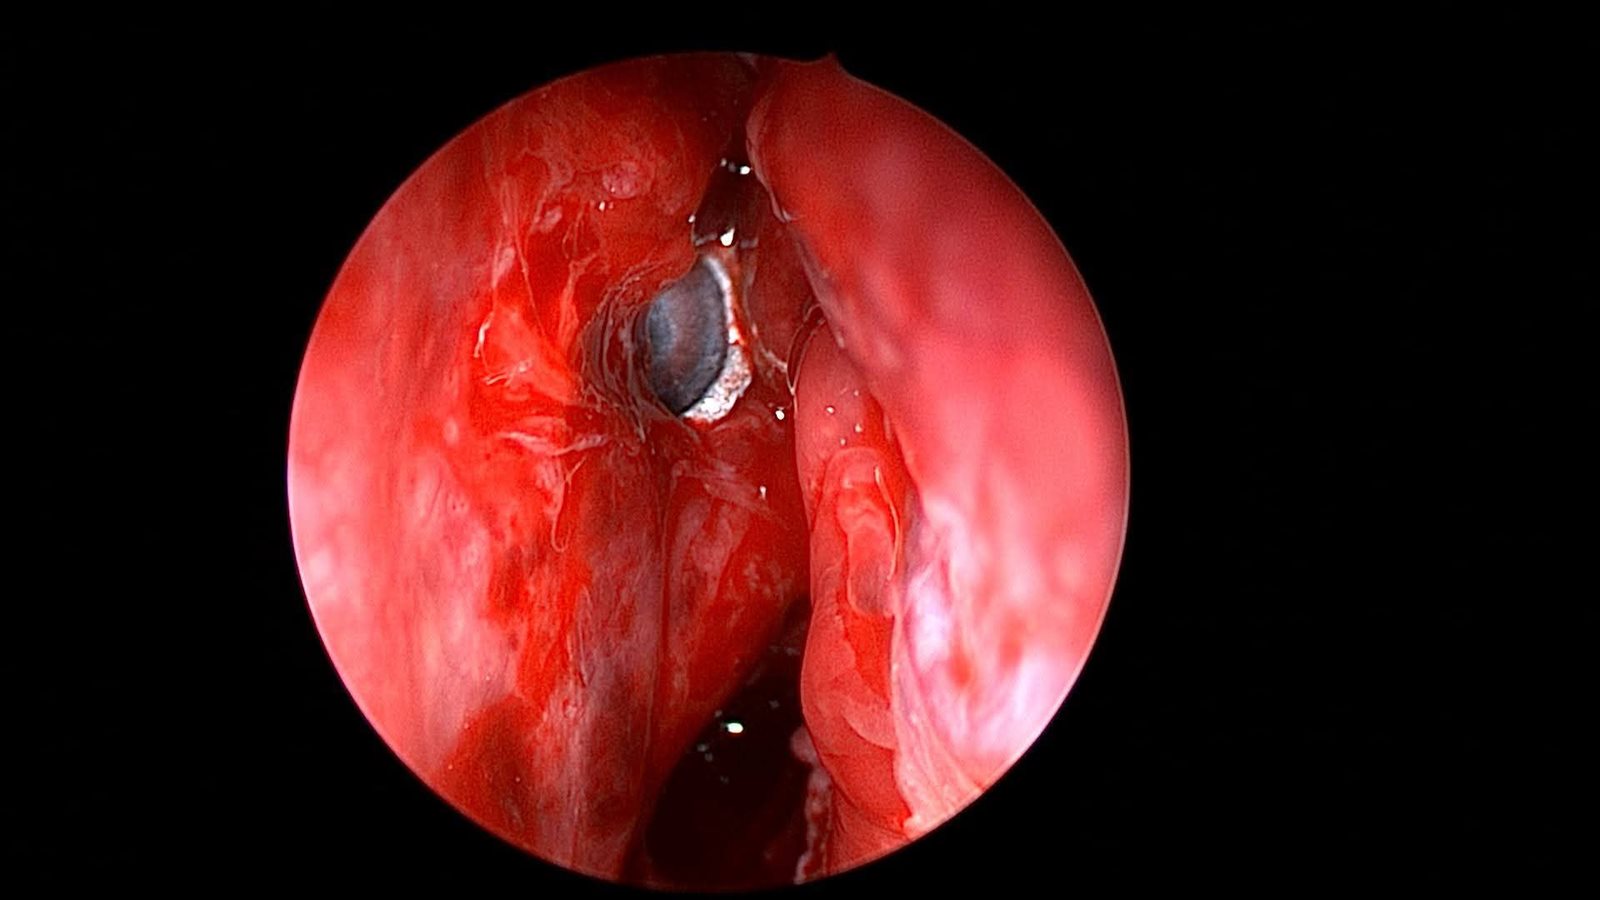

وكانت المريضة قد حضرت إلى المستشفى تعاني من نزيف بالأنف وتورم بالعين، عقب ادعائها الإصابة بطلق ناري من بندقية صيد، وعلى الفور، تم إجراء أشعة مقطعية على الأنف والجيوب الأنفية، والتي أظهرت وجود جسم غريب معدني مستقر داخل الجيوب الأنفية الغربالية.

وعلى إثر ذلك، تم التعامل مع الحالة بشكل عاجل، حيث جرى إدخالها إلى عمليات قسم الأنف والأذن والحنجرة، وتمكن الدكتور علاء عبدالسميع، أستاذ مساعد الأنف والأذن والحنجرة، بمشاركة الفريق الطبي المعاون من أطباء وتمريض العمليات، من استخراج الطلقة بنجاح باستخدام منظار الجيوب الأنفية، دون حدوث أي مضاعفات.